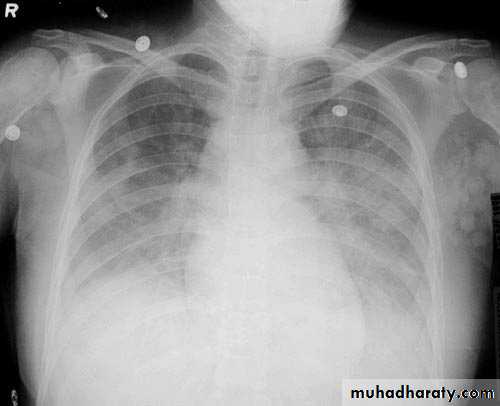

Interstitial pulmonary edema

Pulmonary edema ( alveolar pulmonary edema)

Bat wing sign ( alveolar pulmonary edema)

38.interstial pulmonary edema

39.pulmonary edema ( alveolar pulmonary edema )

40.batwing sign ( alveolar pulmonary edema )